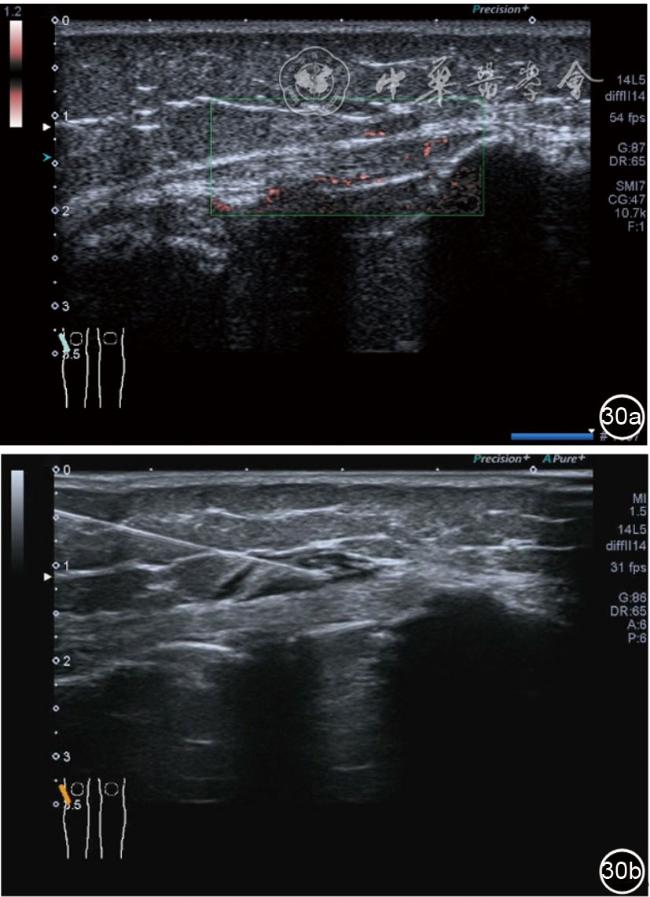

1.髂胫束局部治疗。仍以保守治疗为首选。如物理治疗、口服药物、康复训练等,早期可以超声引导下肌腱表面注射治疗。针刀剥离松解治疗具有创伤小、恢复时间短、感染率低、适应证广,无绝对禁忌证等优势,可作为首选手术方案。(1)髂胫束胫骨附着点表面局部药物注射治疗。患者侧卧位,髋内旋,膝关节屈曲20°~30°,膝下垫枕。局部消毒,铺无菌巾,穿刺区域常规消毒,探头涂抹耦合剂后套入无菌手套碘伏消毒或使用无菌耦合剂,长轴显示髂胫束,找到胫骨附着点病变部位。选用25G针头,抽取1%利多卡因3 ml+曲安奈德10 mg,超声引导下针尖到达肌腱表面进行注射(图28),注射完毕拔出针头,局部压迫2分钟,穿刺点创可贴覆盖。(2)髂胫束股骨外髁附着点局部药物注射治疗。体位及治疗前准备同髂胫束胫骨附着点表面局部药物注射治疗,长轴显示髂胫束,找到股骨外髁附着点病变部位。确定髂胫束与股骨外髁之间为靶点,选用25G针头,抽取1%利多卡因3 ml+曲安奈德10 mg,超声引导下,针尖到达骨表面进行注射(图29),注射完毕拔出针头,局部压迫2分钟,穿刺点创可贴覆盖。(3)髂胫束胫骨附着点局部针刀剥离松解治疗。体位及治疗前准备同髂胫束胫骨附着点表面局部药物注射治疗。超声探头长轴位扫查,根据压痛点和超声显示肌腱变化的位置确定靶点。用1%利多卡因3 ml沿韧带表面及胫骨止点病变部位局部麻醉。选用直径0.6 mm的Ⅰ型2号针刀由近端向远端平面内进刀,平刀在韧带表面剥离松解3~5刀,然后进入胫骨附着点损伤处进行剥离松解3~4刀拔出针刀(图30),局部压迫止血5分钟,无菌敷料覆盖。(4)髂胫束股骨外髁附着点局部针刀剥离松解治疗。体位及治疗前准备同髂胫束胫骨附着点表面局部药物注射治疗。超声探头长轴位扫查,根据压痛点和超声显示肌腱变化的位置确定靶点。用1%利多卡因3 ml沿股骨外髁部位的髂胫束表面局部麻醉。选用直径0.6 mm的Ⅰ型2号针刀由近端向远端平面内进刀,平刀在髂胫束表面剥离松解3~5刀拔出针刀(图31),局部压迫止血5分钟,无菌敷料覆盖。

图30 超声引导下髂胫束胫骨附着点局部针刀剥离松解治疗